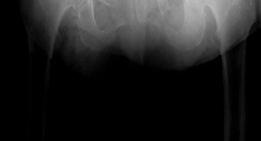

Clinical & Radiographic Imaging